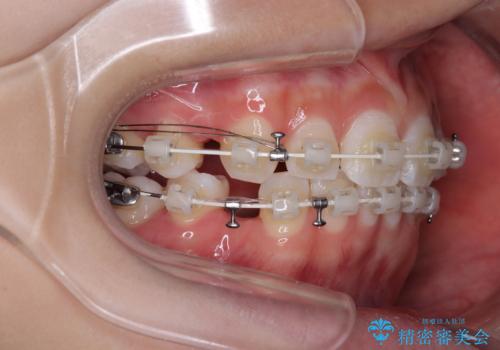

- 矯正装置

- 審美装置

- 2年

- 10-30回